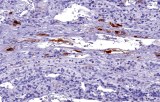

CE/IVD antibodies for immunohistochemistry (IHC) in neuropathology are validated in vitro diagnostic reagents used to detect specific neuronal and glial antigens in formalin-fixed paraffin-embedded (FFPE) tissue. Peer-reviewed neuropathology literature supports their role in improving reproducibility and diagnostic accuracy in central nervous system (CNS) diseases, including brain tumors and neurodegenerative disorders.

Targeted proteins such as GFAP, OLIG2, NeuN, synaptophysin, neurofilament, and Iba1 reflect astrocytic, oligodendroglial, neuronal, and microglial lineages. Their expression patterns are widely used in peer-reviewed studies to define CNS cell identity, differentiation state, and neuroinflammatory or degenerative processes.

CE/IVD IHC antibodies support CNS tumor classification (gliomas, embryonal tumors, metastases), assist in differential diagnosis, and help identify proteinopathies associated with Alzheimer’s disease and other neurodegenerative conditions. They are routinely used in biomarker panels for tumor grading and diagnostic stratification in neuro-oncology.